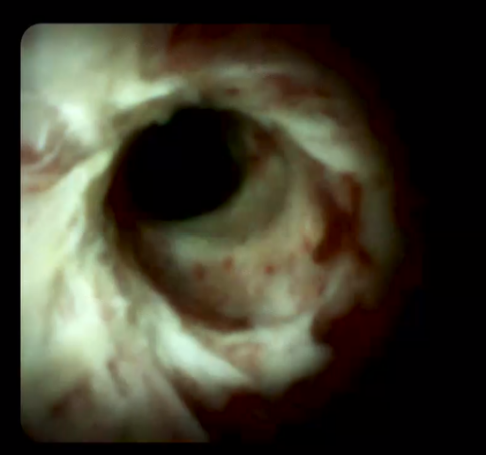

另外,經口膽道子鏡光纖直視系統(SPYGLASS)是一種電子膽道子鏡,可通過十二指腸鏡到達膽管或胰管內,對病變進行直視觀察,高清高分辨率顯示病變、并精準指導活檢,對于膽胰管狹窄的診斷治療具有重要意義。

經口膽道鏡下膽總管碎石

經口膽道鏡下膽管組織活檢